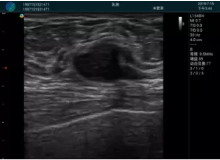

腺體內(nèi)部清晰顯示一低回聲塊影,形態(tài)不規(guī)則,邊界模糊,邊緣呈毛刺狀,內(nèi)部見砂礫樣鈣化

M20引導(dǎo)下穿刺活檢術(shù)